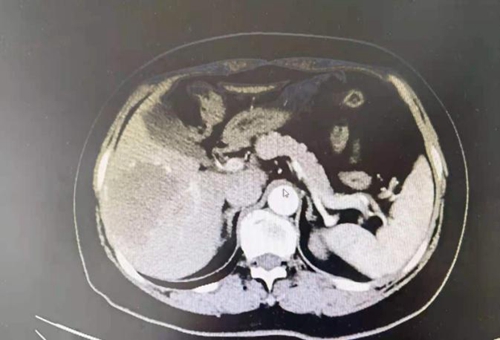

一個(gè)月前,59歲的張阿姨(化名)因?yàn)榧毙晕秆椎疆?dāng)?shù)蒯t(yī)院就診,CT檢查時(shí)發(fā)現(xiàn)自己右肝有85mm×70mm×50mm的腫瘤占位,急壞了一家人。

其中6,7段為肝臟右后葉

肝血管瘤是肝內(nèi)血管結(jié)構(gòu)發(fā)育異常所導(dǎo)致的良性腫瘤,多為海綿狀血管瘤。肝臟是人體腹腔內(nèi)最大的實(shí)質(zhì)性器官,組織結(jié)構(gòu)脆弱,血流豐富,而張阿姨的腫瘤位于特殊位置,一旦發(fā)生破裂,就有可能出現(xiàn)難以控制的大出血甚至危及生命。

張阿姨害怕腫瘤繼續(xù)增大會(huì)有不良后果,想要手術(shù)摘除腫瘤,但又懼怕傳統(tǒng)開腹手術(shù)創(chuàng)傷大、恢復(fù)慢。肝膽外科團(tuán)隊(duì)積極組織科內(nèi)討論,對(duì)各項(xiàng)檢查結(jié)果進(jìn)行分析和討論,決定為張阿姨實(shí)行“腹腔鏡下肝右后葉切除術(shù)”。